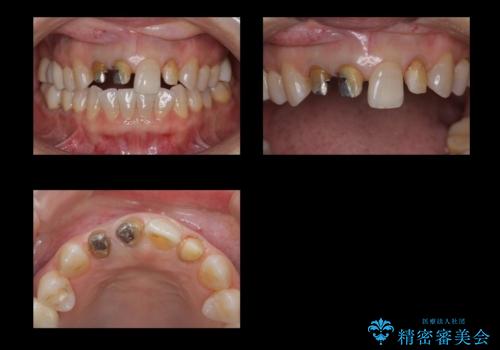

- 前歯のかぶせ物の際が黒いことを気にされて来院。

左上のかぶせ物になっていない歯は根の先に膿がたまっていたので根の治療をし、プラスチックでつぎはぎになっていたためセラミッククラウンでかぶせました。

- 61.6万円 内訳:右上12および左上2(ジルコニアクラウン14万円×3 仮歯1万円×3) 左上2(再根管治療 9万円、ファイバーコア2万円) 費用は治療当時の料金となります

右上12の二本の根の治療は特に行っておらずクラウンのみやり替えを行いました。